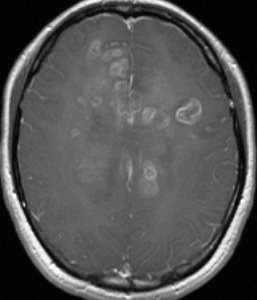

35歳,側頭葉てんかんで発症した右側頭葉の乏突起膠腫 グレード2です。全摘出して化学療法4コースと54グレイの局所放射線治療 generous local fieldを行いました。7年後に同じ部位に再発して摘出したところ退形成性乏突起膠腫 グレード3となっていました。手術摘出して,テモゾロマイド化学療法で維持療法をしていました。

その2年後の画像です。右小脳半球に再発しています。右側頭葉腫瘍との連続性は全くありませんでした。脳幹部にも腫瘍はありません。遠隔再発 remote recurrenceというもので,星細胞系腫瘍 astroytic tumor AAやGBMではよく知られている現象です。乏突起膠細胞系腫瘍でもまれにみられます。

だからと言って初期治療で広範囲放射線治療をした方がいいということにはならず,これを避ける手段はありません。